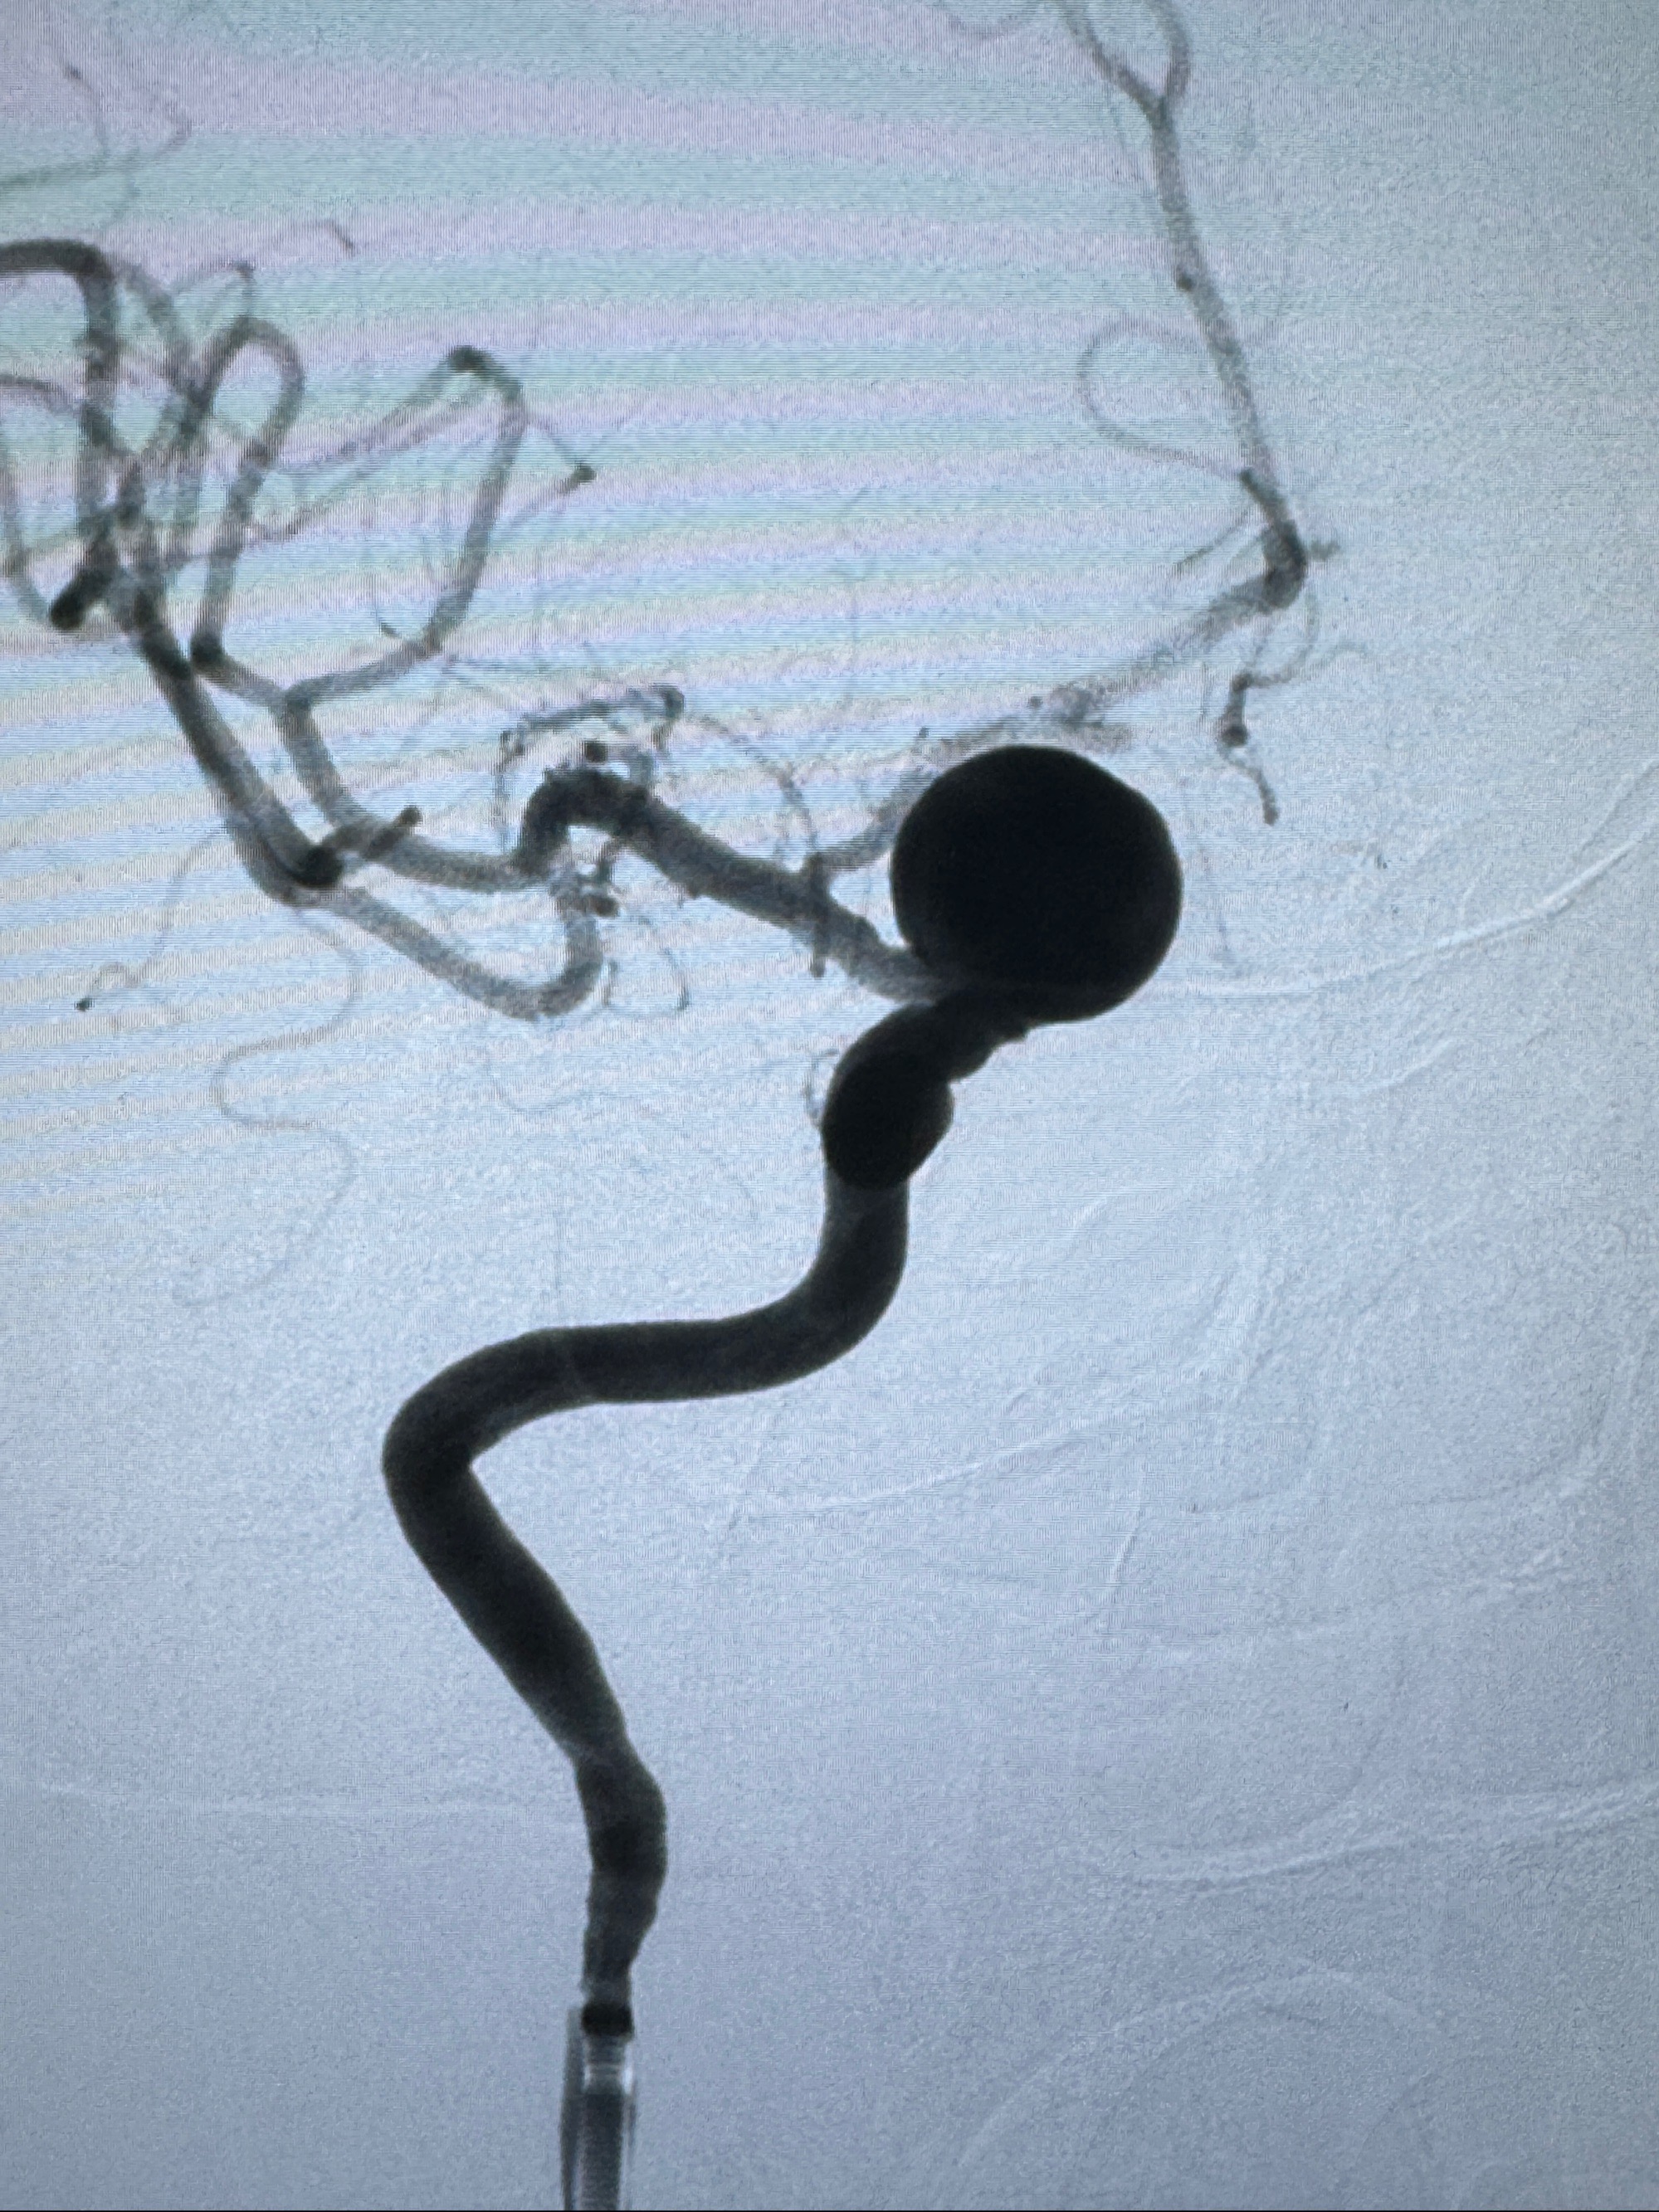

现病史:患者诉2年来反复发作性头痛,顶枕部为主,因自己考虑高血压可能,未予系统检查;患者约20日前无明显诱因下突发剧烈头晕,有天旋地转感,不能睁眼,伴视物模糊;外院查头颅MRI+MRA提示:左侧颈内动脉C6段动脉瘤;遂至复旦大学附属华山医院就诊,于2023-12-08行全脑血管造影提示:右侧颈内动脉C6段动脉瘤,瘤颈6.68mm,动脉瘤大小13.28*12.34mm,建议行密网支架辅助栓塞术治疗,因缺乏相关材料遂出院。现患者仍有顶枕部头痛不适,为求进一步诊疗脑血管病变至我科就诊,收治入院。

2023-12-08 复旦大学附属华山医院 全脑血管造影:右侧颈内动脉C6段动脉瘤,瘤颈6.68mm,动脉瘤大小13.28*12.34mm

初步诊断:1.右侧颈内动脉眼动脉段动脉瘤

2023-12-08外院DSA:右侧颈眼动脉瘤,约13*12mm大小,压颈试验显示左右向及后向前代偿可